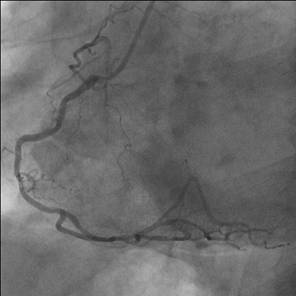

Ziel der Operation ist, jeder höhergradige Stenose an relevanten Coronarästen (Abb.1.) mittels Bypass zu überbrücken, es wird somit über arterielle oder venöse Bypässe in die zuvor minderversorgten Areale wieder ausreichend Blut transportiert (Abb. 2.). Triviale Äste können jedoch wegen ihres kleinen Durchmessers nicht versorgt werden. Der aortocoronare Mehrfachbypass unter Verwendung der Arteria thoracica interna (linke innere Brustarterie) ist heute absoluter Standard an jeder herzchirurgischen Klinik und die häufigste Herzoperation weltweit (Abb.3.).

Abb. 1. Darstellung der Herzkranzgefäße mittels Coronarangiographie (rechte und linke Kranzarterie) zur Beurteilung von Engstellen (Stenosen) vor einer allfälligen Intervention.